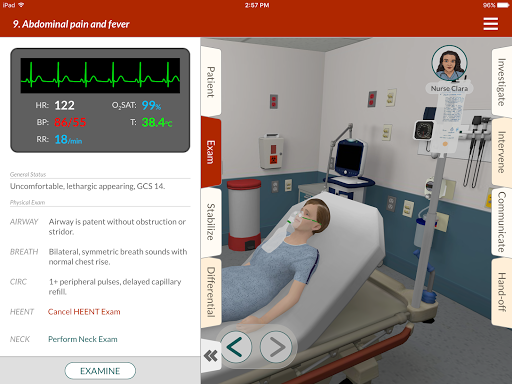

• 200+ thư viện trường hợp được biên soạn và đánh giá bởi các bác sĩ lâm sàng chuyên gia

• Hơn 30 chuyên khoa chẩn đoán, bao gồm Y học cấp cứu, Sản phụ khoa và Nhi khoa

• AI của bệnh nhân cho phép thực hành với việc ghi lại bệnh sử

- Ho & Đau -

Bệnh nhân của Full Code sẽ ho rõ ràng và rõ ràng khi thích hợp, đồng thời trông không vui và nhăn mặt khi họ khó chịu hoặc đau đớn.

- Mất

bù của bệnh nhân - Trong một số trường hợp, bệnh nhân sẽ trở nên tồi tệ hơn (mất bù) theo thời gian khi bệnh tiến triển.